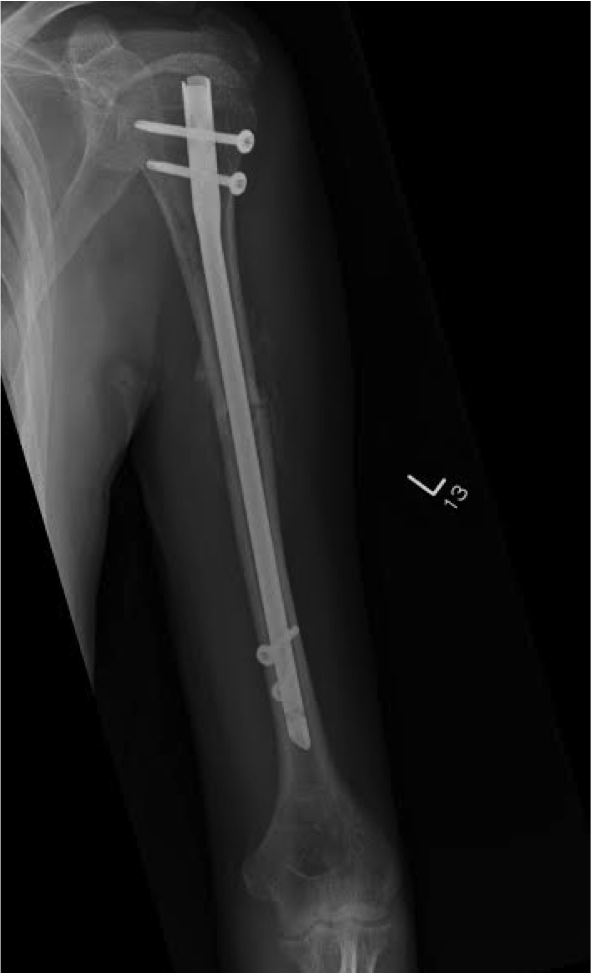

Humeral Shaft Fracture Fixation What To Do With Broken Humerus a fractured humerus is common and may result from injury. Where you can feel hot and cold. the main aim of treatment is to prevent stiffness, reduce pain and restore function. if you have a fractured humerus you will have a collar and cuff which may include a plaster or brace depending on where the. Use your. What To Do With Broken Humerus.